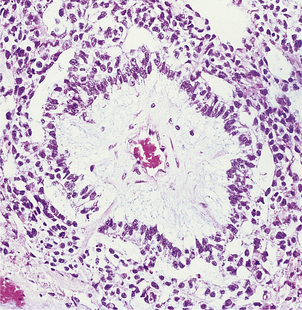

Granulomatous prostatitis

Granulomatous prostatitis is a heterogeneous group of lesions, all of which may cause enlargement of the gland and urethral obstruction. The inflammatory component and associated fibrosis produce a firm, indurated gland on rectal examination which may mimic a neoplasm clinically, thus highlighting the importance of correctly diagnosing this uncommon group of conditions.

Idiopathic prostatitis may result from leakage of material from distended ducts in a gland enlarged by nodular hyperplasia. There is a periductal inflammatory infiltrate which includes macrophages, multinucleated giant cells, lymphocytes and plasma cells, with associated fibrosis.

The prostate is often involved in cases of genito-urinary tuberculosis. This condition is usually secondary to tuberculous cystitis or epididymitis, the infection spreading along the prostatic ducts or vas deferens. The histological features are of caseating granulomas distributed among the prostatic glands and through the stroma.